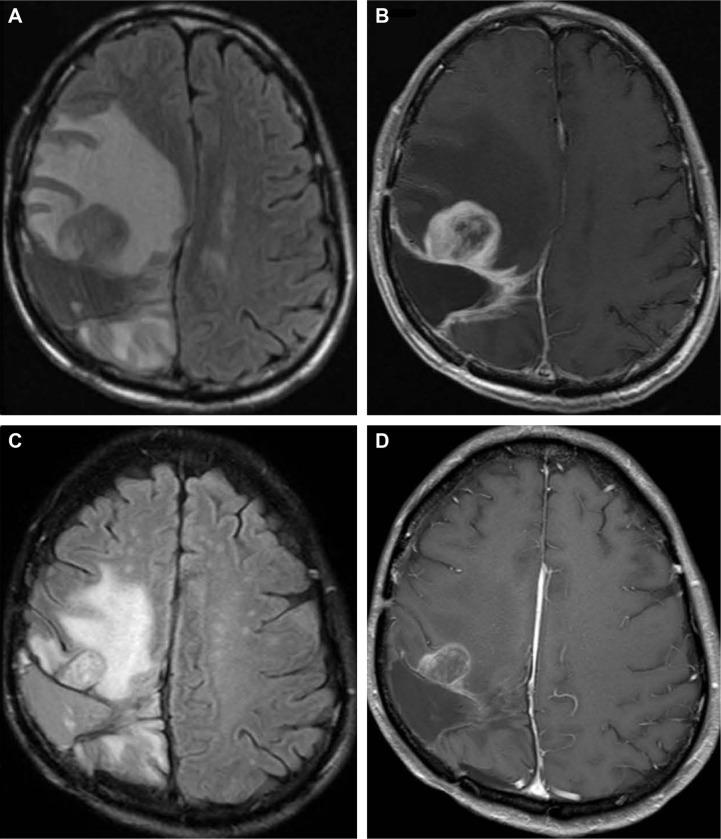

Malignant glioma (MG) is a common and refractory primary tumor with a high recurrence rate. There is still a lack of effective therapy for recurrent MG (rMG). We present here two cases of refractory rMG treated using apatinib, which is a new highly selective inhibitor to VEGFR. Case 1, a 37-year-old female, was diagnosed with recurrent intracerebral high-grade glioma and failed to almost all treatments (including temozolomide, bevacizumab, nimotuzumab, reradiation, etc) during her second relapse. Case 2, a 40-year-old male, was diagnosed with recurrent glioblastoma multiforme for the third time following multiple treatments including resurgery, temozolomide and radiation. These two patients were treated with oral apatinib (500 mg daily) during their most recent relapse and experienced rapid relief of central nervous system symptoms. Case 1 achieved near complete response evaluated by magnetic resonance imaging (MRI) after 6, 12 and 20 weeks medication and had an overall survival of 27 weeks. Case 2 achieved partial response evaluated by MRI after 4 and 12 weeks medication and had a progression-free survival of 12 months. The preliminary results of these two cases indicate that apatinib has outstanding efficacy for refractory rMG. It is worthwhile to develop a Phase II clinical trial to further evaluate the efficacy and toxicity of apatinib for rMG.

恶性胶质瘤(MG)是一种常见且难治的原发性肿瘤,复发率很高。复发性MG(rMG)仍然缺乏有效的治疗方法。我们在此介绍两例使用阿帕替尼治疗的难治性rMG病例,阿帕替尼是一种新型的高度选择性血管内皮生长因子受体(VEGFR)抑制剂。病例1,一名37岁女性,被诊断为复发性脑内高级别胶质瘤,在第二次复发时几乎对所有治疗(包括替莫唑胺、贝伐单抗、尼妥珠单抗、再放疗等)均无效。病例2,一名40岁男性,在接受了包括再次手术、替莫唑胺和放疗在内的多次治疗后,第三次被诊断为复发性多形性胶质母细胞瘤。这两名患者在最近一次复发时接受了口服阿帕替尼治疗(每日500毫克),中枢神经系统症状迅速缓解。病例1在用药6周、12周和20周后通过磁共振成像(MRI)评估达到近乎完全缓解,总生存期为27周。病例2在用药4周和12周后通过MRI评估达到部分缓解,无进展生存期为12个月。这两例的初步结果表明,阿帕替尼对难治性rMG有显著疗效。开展一项II期临床试验以进一步评估阿帕替尼对rMG的疗效和毒性是值得的。